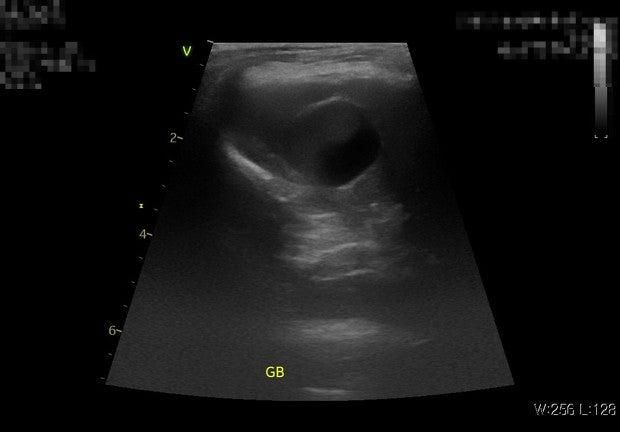

• 1번 째 사진